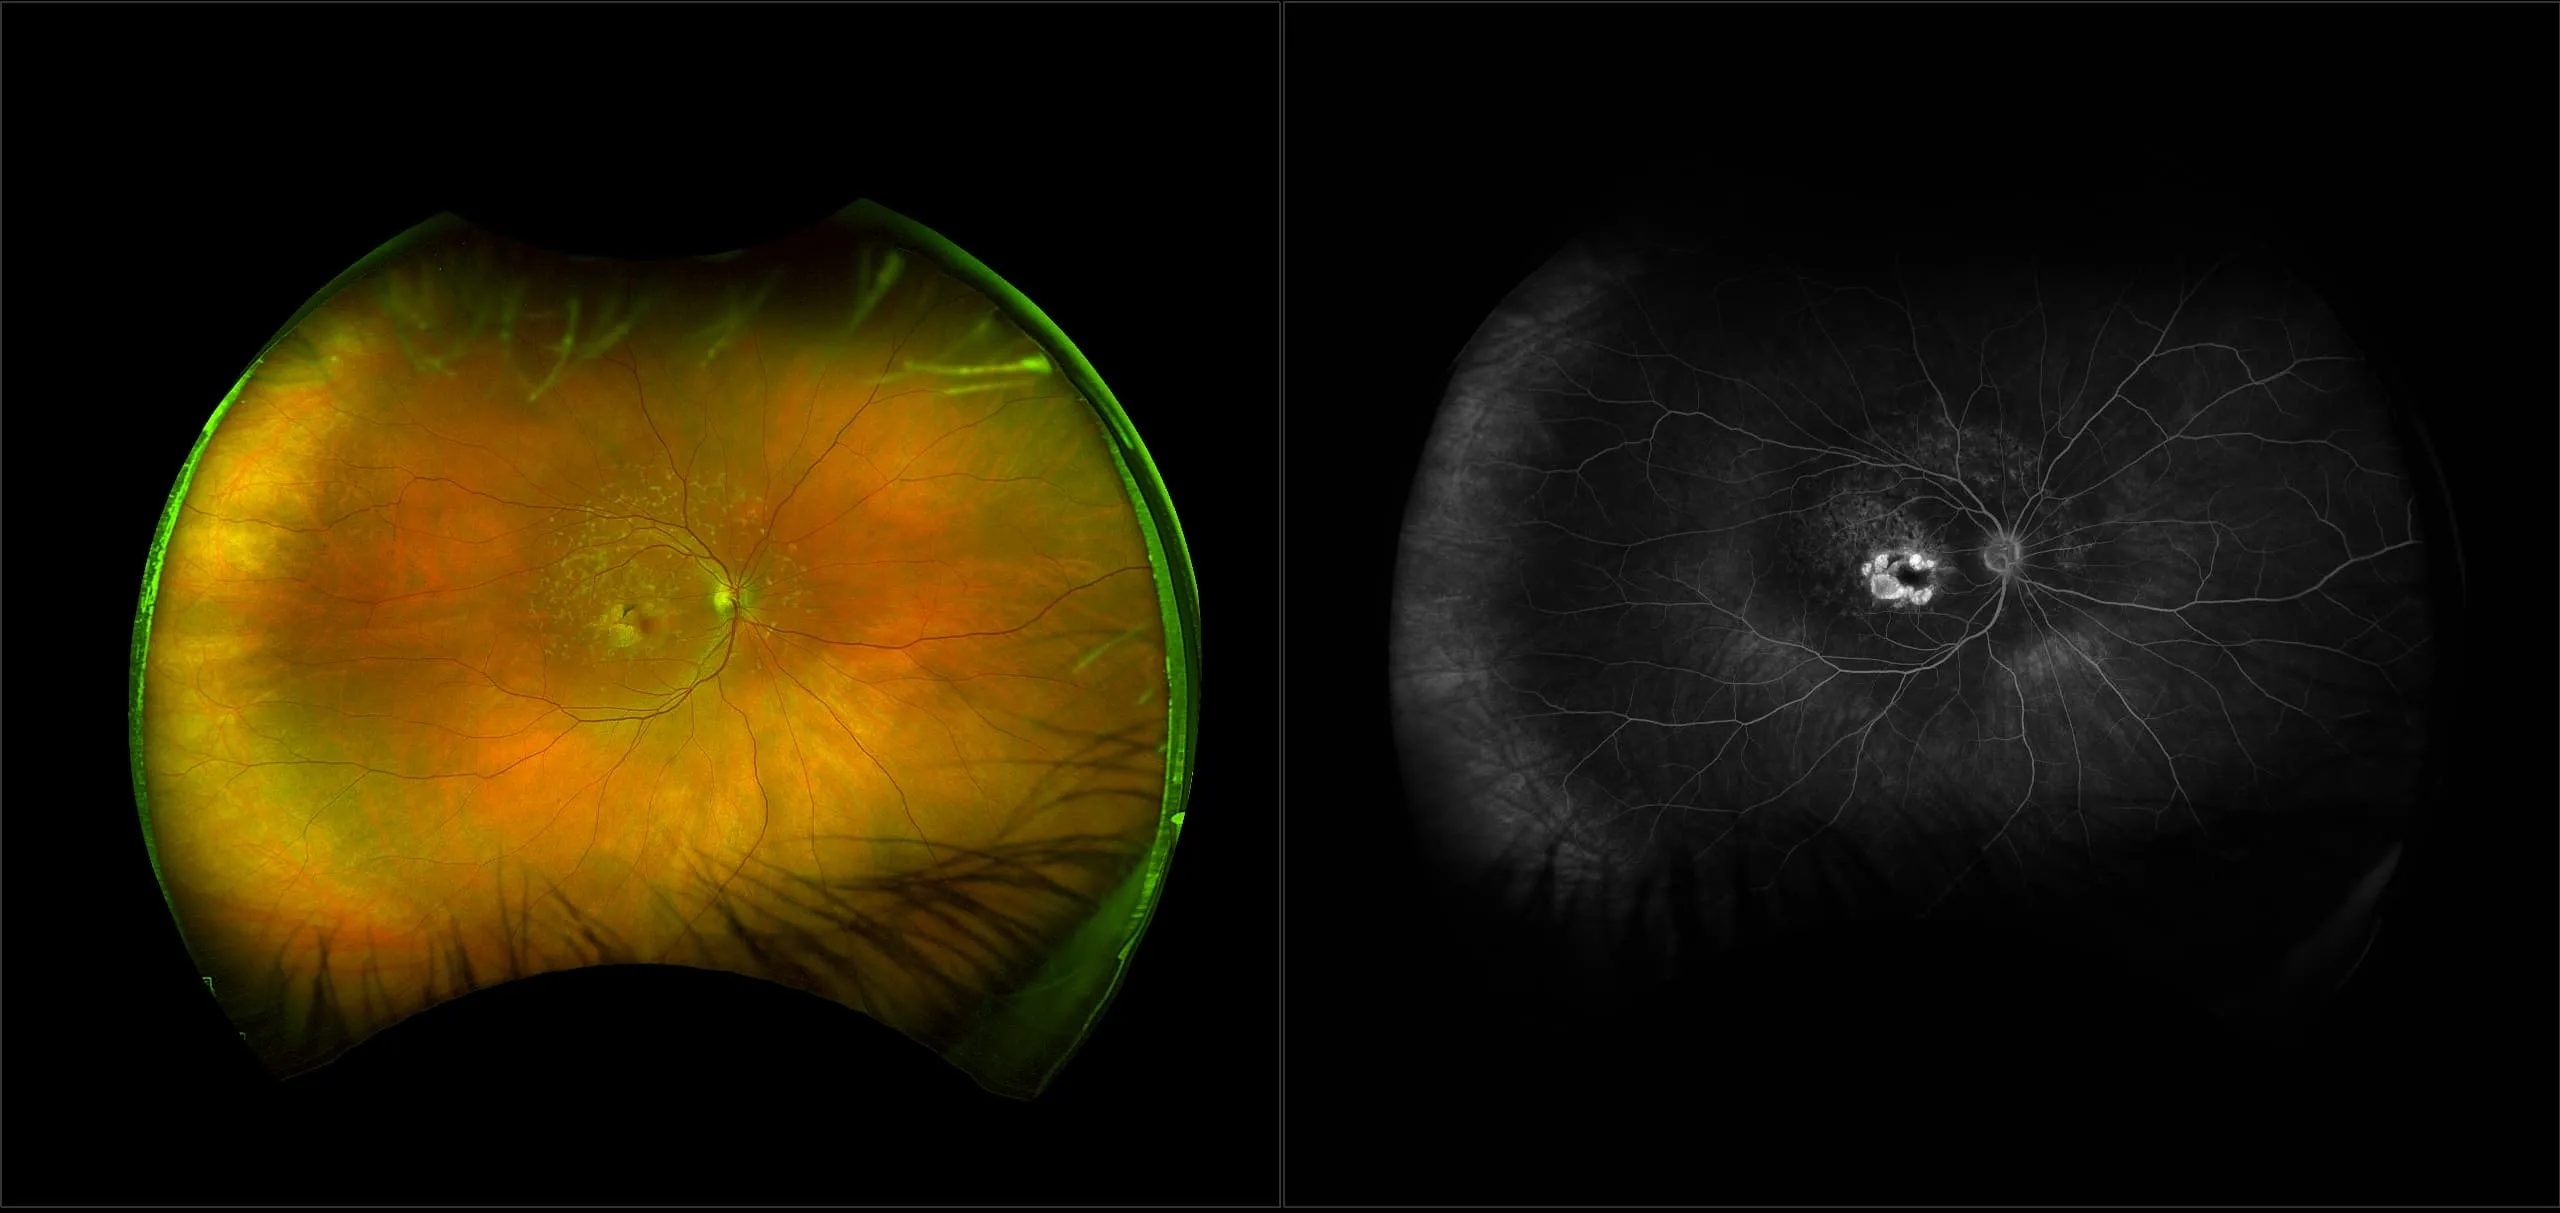

optomap® Recognizing Pathology

This material is designed as a searchable reference resource to support clinical decision-making. The information contained here should be used as general guidance when viewing optomap and OCT images from Optos devices. The differential diagnosis should be made under the direction of the responsible physician. These images were taken on the latest ultra-widefield optomap devices.

The Cases and Images

optomap Recognizing Pathology is searchable by pathology and/or optomap image modality. You may search by multiples of each selection. Each individual case is represented by the accompanying thumbnail image. Most cases include several different optomap image modalities. To view a full description of the case, please click on the thumbnail. Each image in the case will be made available through our OptosAdvance software which provides multi-dimensional visualization of digital images to aid in the analysis of anatomy and pathology. Support and pathology definitions can be found by selecting one of the buttons, above. Should you have questions, please complete the form below.